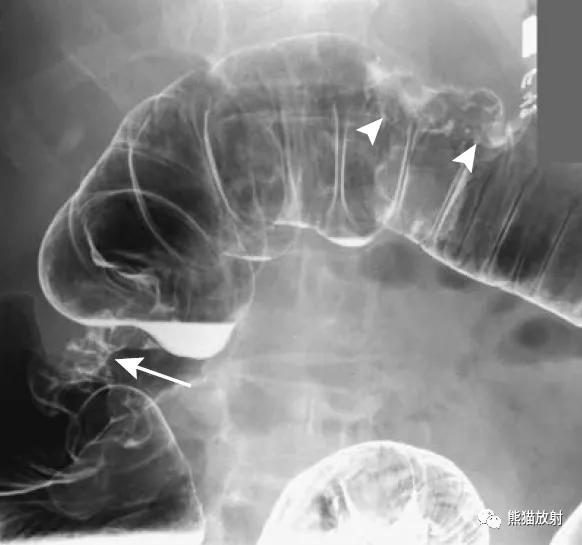

直肠远端癌(小箭),呈弥漫性地毯样浸润。息肉状浸润性直肠癌(大箭)。

直肠周围脓肿(易误诊为直肠癌)。4个月前因增生行前列腺切除术,出现便秘。盆腔CT显示直肠病变并管腔变窄(箭头)。T1和T2加权图像显示直肠壁增厚和周围充满液体的结构(箭),提示脓肿或坏死性肿瘤。

疑急性阑尾炎的患者,右半结肠癌并穿孔(箭头)。周围软组织肿块内坏死并气体影,类似阑尾脓肿表现。

直肠癌。平扫和增强的冠状T1WI图像显示远端直肠左侧壁肿瘤(箭头)侵犯直肠周围脂肪。

乙状结肠腺癌(箭头)。1cm圆形肿瘤,边缘光滑,其内的小圆圈是肿瘤的蒂。